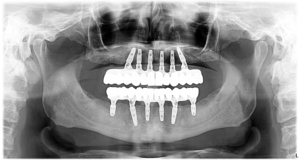

În 2023  Domnul P. s-a hotărât să își recapete zâmbetul, afectat de multiple complicații de-a lungul anilor.  Acesta purta o proteză mobilă ce îi îngreuna atât viața socială, cât și procesul masticator și, implicit, și cel digestiv.Domnul P. ne-a mărturisit că nu știa cum își poate recăpăta sănătatea dentară, deși căutase multe variante, așa că s-a bucurat enorm când a ajuns în clinica noastră. În urma consultației inițiale am redactat un plan de tratament personalizat pentru situația sa dentară, ce cuprindea:

• Inserarea a 6 implanturi dentare la maxilar

• Inserarea a 6 implanturi dentare la mandibula